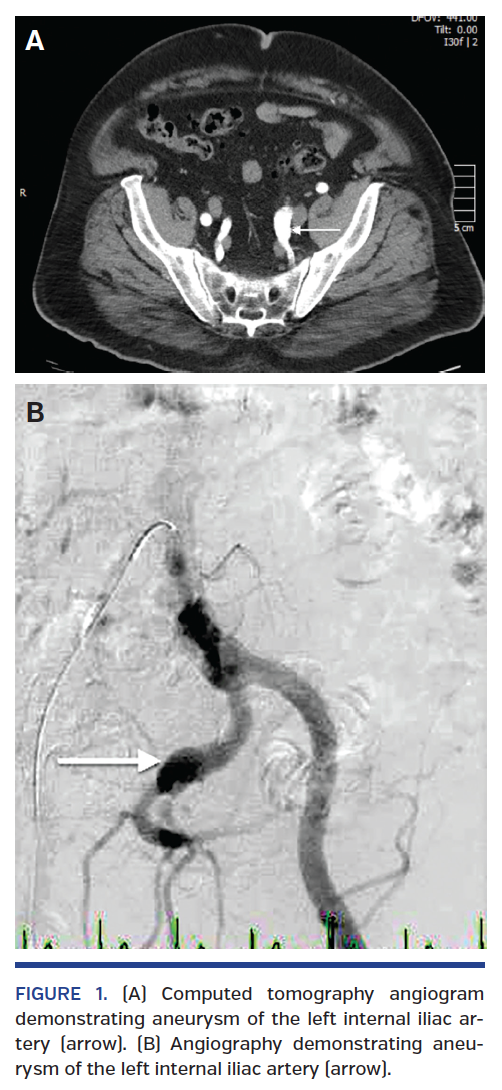

Fluoroscopy of the mechanical aortic valve in orthogonal views confirmed severely restricted valve leaflets. Coronary angiogram revealed normal, right-dominant coronary

anatomy with a thrombotic subtotal occlusion of the left anterior descending (LAD) artery and first diagonal branch bifurcation with Thrombolysis in Myocardial Infarction (TIMI) 2 flow into both territories (Figure 2). Thrombectomy of the LAD was performed using an Export catheter (Medtronic, Minneapolis, Minnesota) with 3 passes followed by thrombectomy of the diagonal branch with 5 passes, retrieving large pieces of thrombi (Figure 3). Final angiograms revealed a small residual thrombus in the mid-segment of the diagonal branch with TIMI 3 flow to both LAD and

diagonal territories (Figure 2). Right heart catheterization revealed elevated pressures with a pulmonary artery pressure of 70/25 mmHg and a mean pulmonary capillary wedge pressure of 30 mmHg.